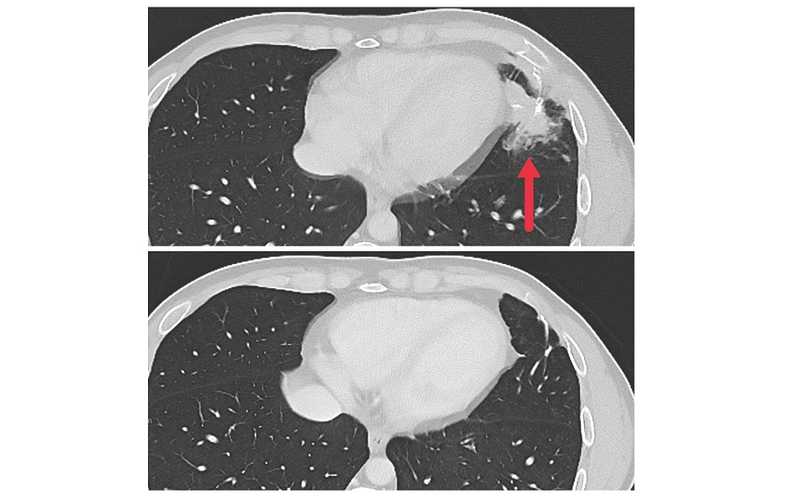

Трое пациентов достигли непродолжительного частичного ответа на терапию, выраженного в регрессии очагов метастазирования в печени, легких и лимфатических узлах. Медиана выживаемости без прогрессирования составила 4,6 месяца. Ответ на терапию зависел от источника неоантиген-реактивных TCR. Пять из семи пациентов получили TCR, выделенные из CD4+ T-клеток, только один из которых достиг частичного ответа на терапию. Оба пациента, получавших TCR, выделенные из CD8+ Т-клеток, достигли частичного ответа на терапию.